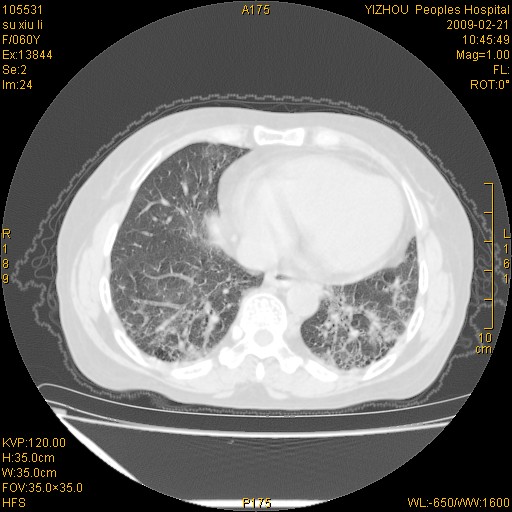

标题: CT18259:两肺间质纤维化? [打印本页]

标题: CT18259:两肺间质纤维化?

女,60岁,反复咳嗽1月。

两肺支扩,以肺为著合并双肺较广范纤维化病变。建议除外结核等病变。

间质性肺炎

符合间质感染,部分纤维化表现

特发性间质纤维化

特发性间质纤维化伴支扩!

间质性肺炎或特发性间质性肺炎